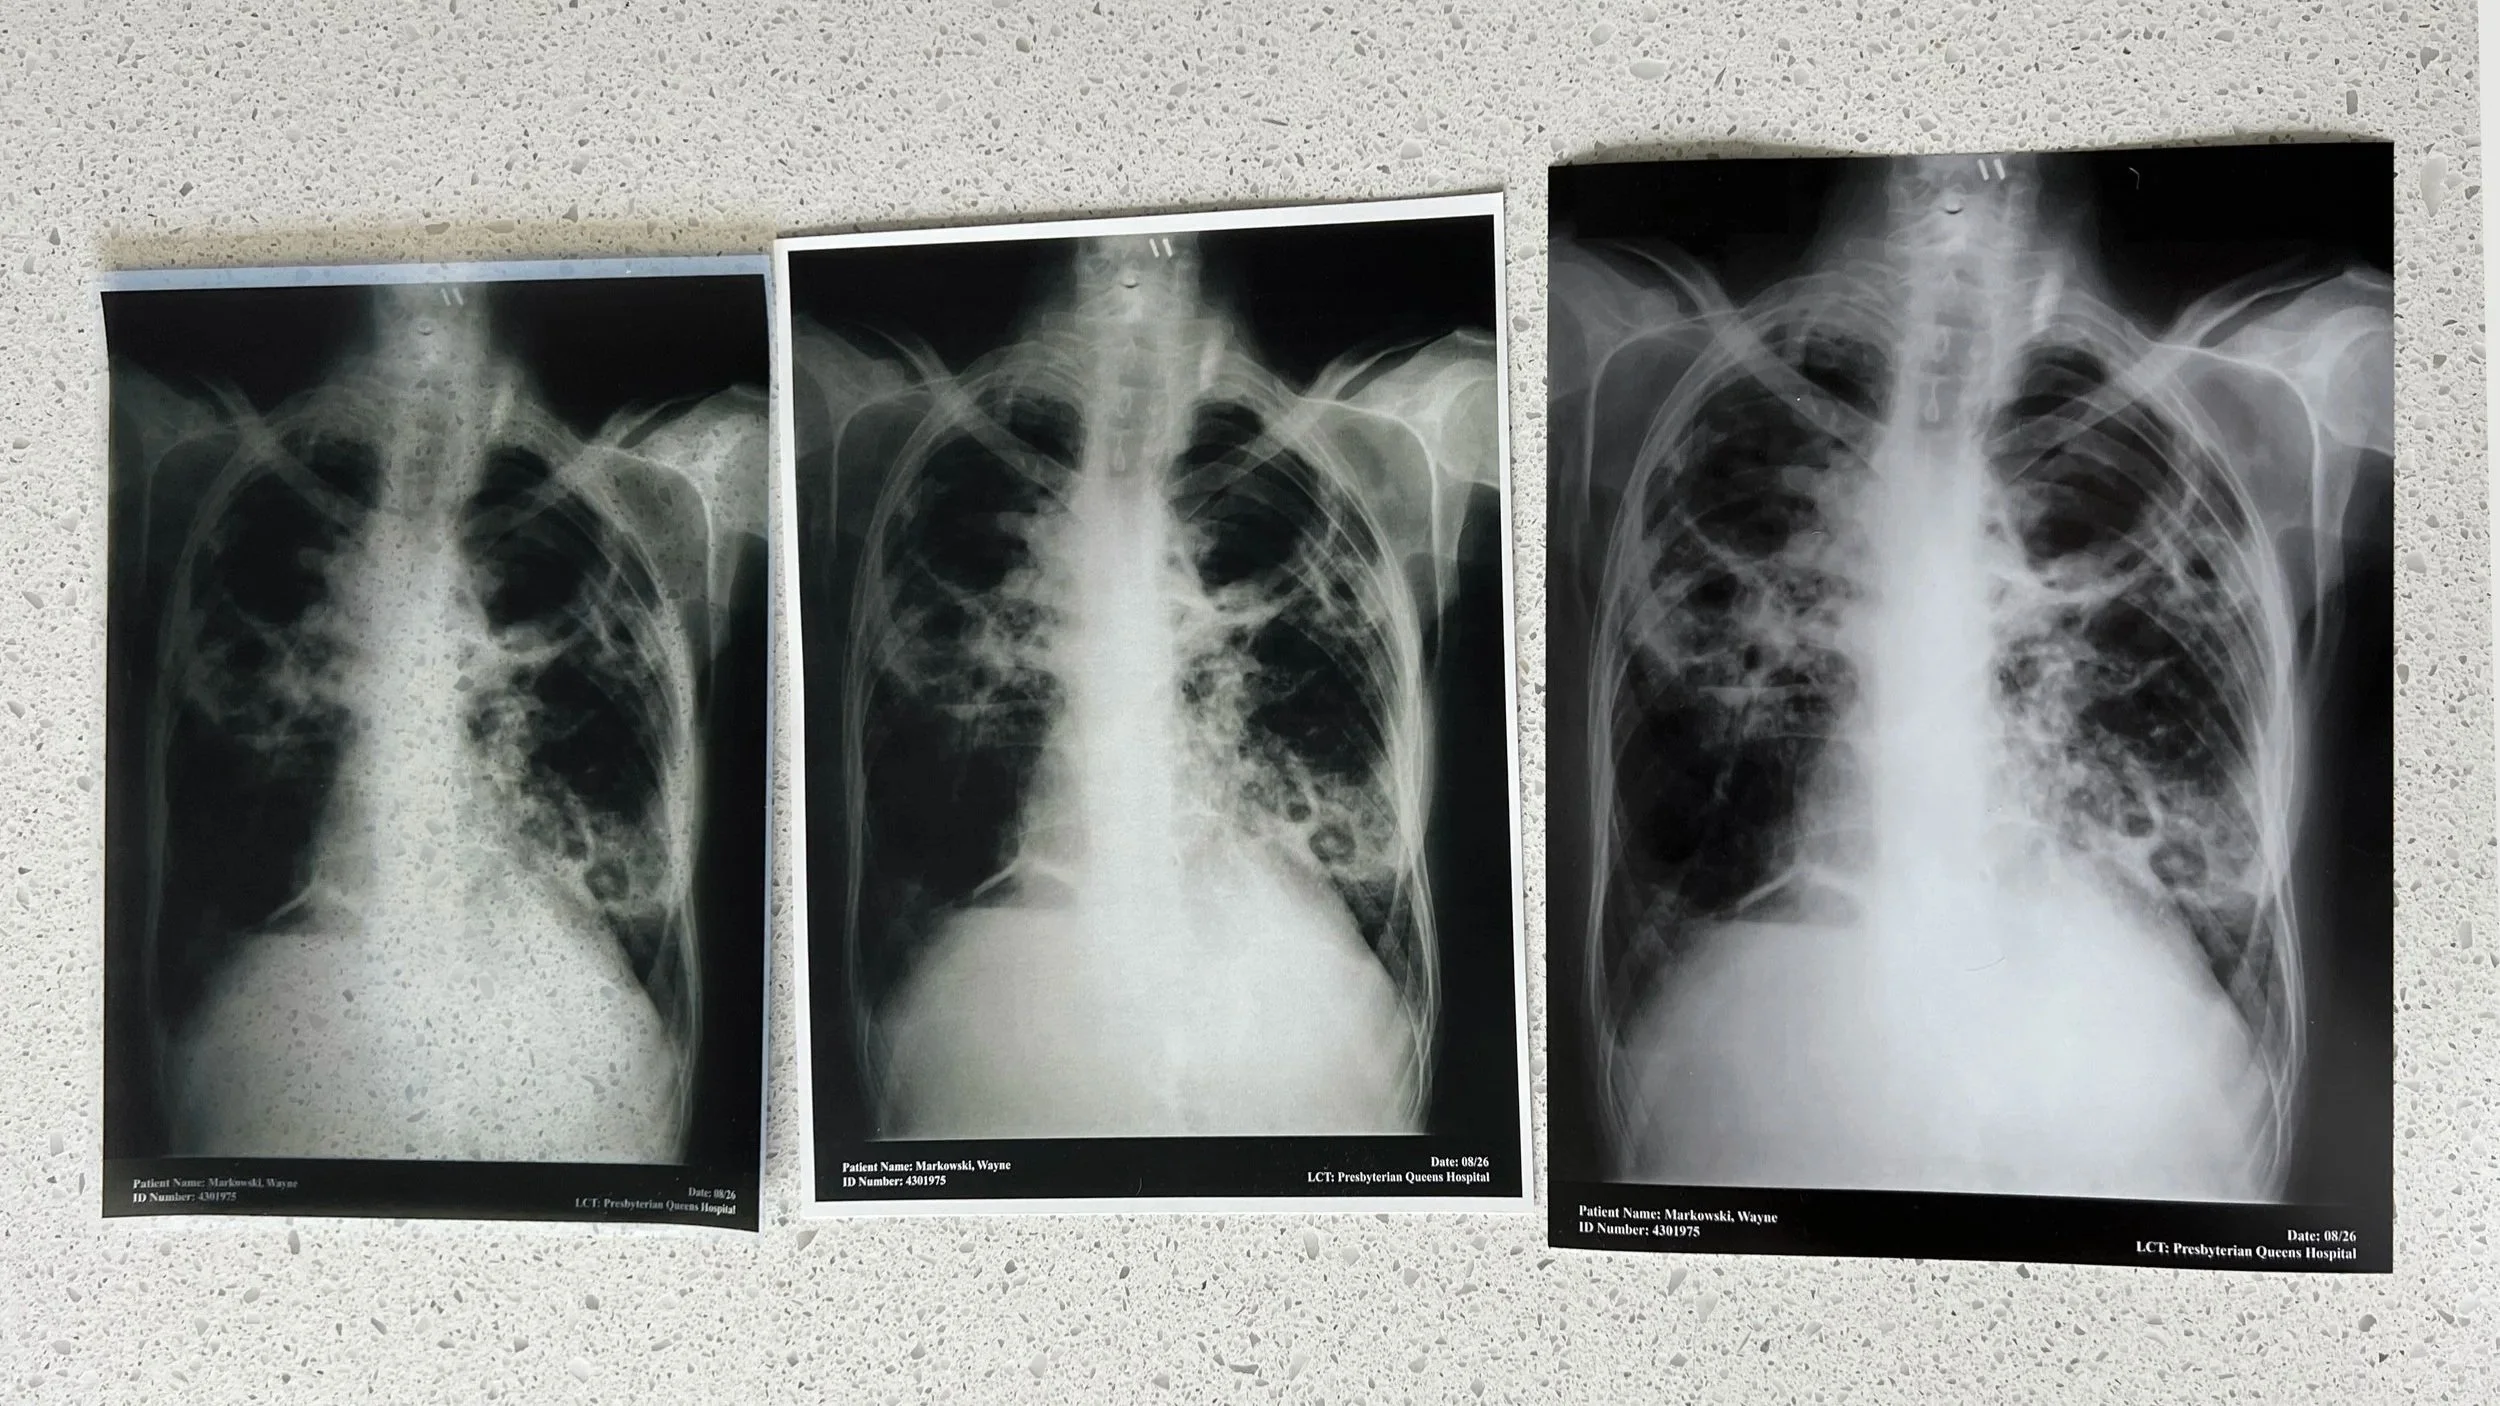

Cleared Art - Chest x-ray Prints